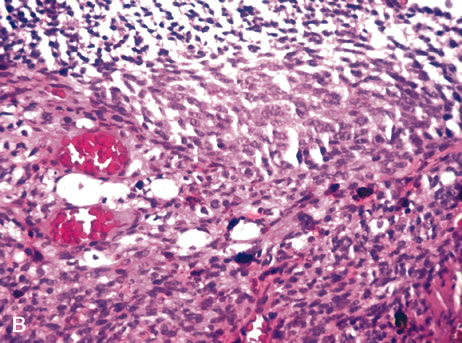

Inflammatory conditions may also lead to iris nodules. Patients suffering from fungal endophthalmitis may demonstrate an irregular yellow-white mass on the iris. Histologically, these appear as necrotizing granulomas containing mycotic agents (Fig. 2). In juvenile xanthogranuloma, a yellowish-gray iris lesion may be associated with spontaneous hyphema, and histopathologically the nodules demonstrate diffuse histiocytic infiltrate (Fig. 3). Multinucleated giant cells displaying peripheral foamy cytoplasm are also noted; these cells are known as Touton giant cells.29 The giant cells and the histiocytes contain lipid that can be demonstrated by oil red O stain.

Fig. 2. Coccidioidomycosis. Iris stroma shows necrotizing granuloma containing mycotic organisms. The organisms show features of Coccidioides immitis. (Hemotoxylin-eosin ×60.)